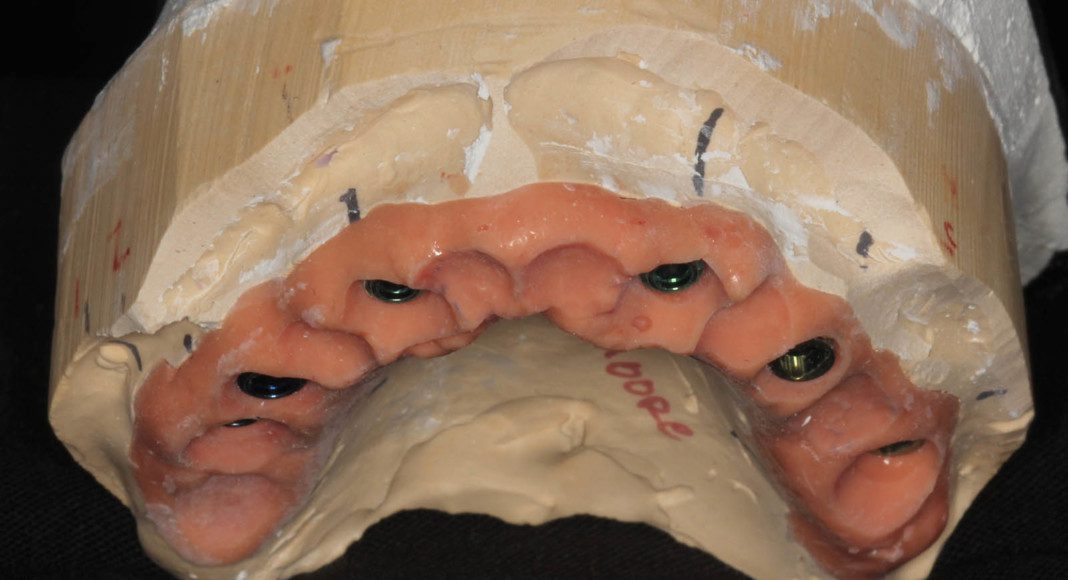

Frontal view of the converted temporary bridge (converted from all teeth supported to all implant supported). The titanium tops are the cylinders that connect the bridge to the implants.

Tissue-view of the converted temporary bridge (converted from all teeth supported to all implant supported). The titanium tops are the cylinders that connect the bridge to the implants.